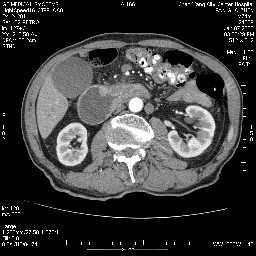

女,74岁,呕吐10余日

壶腹部的占位性病变,考虑为十二指肠癌并梗阻,但脾内多发性低密度区为转移吗?

还有胃、脾之间可见有侧支循环建立。左肾盂积水。

考虑来源于十二指肠水平段的恶性占位,侵及周围组织,特别是胰腺,可见区域淋巴结肿大,左侧下腔静脉畸形。

十二指肠水平段腔内占位伴梗阻,中等度较为均匀的强化,洗脱慢,区域淋巴结显示增多,符合腺癌表现。下腔静脉变异。

十二指肠降段扩张,水平段狭窄成鼠尾状,肠壁明显增厚,胰腺勾突增大成不均匀强化,其内可见低密度区,胆囊增大,1十二指肠水平段腺癌侵犯胰腺勾突可能大,2胰腺癌侵犯十二指肠(只有胆囊增大没有肝内外胆管扩张不好解释)代除外.

十二指肠降段扩张,水平段狭窄成鼠尾状,肠壁明显增厚,胰腺勾突增大成不均匀强化,其内可见低密度区,胆囊增大,1十二指肠水平段腺癌侵犯胰腺勾突可能大,2胰腺癌侵犯十二指肠 。

今日手术结果:胰腺钩突癌侵犯十二直肠,腹腔淋巴结转移.